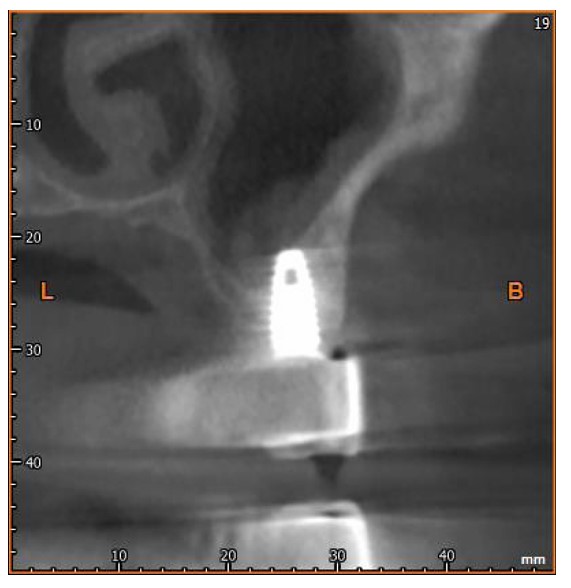

After six months, the implants were exposed, healing abutments were placed, and prosthetic procedures began (Figs. 3 and 4). The RFA of the implant within the lesion revealed a measurement of 83.

CBCT scan 12 months after surgery.